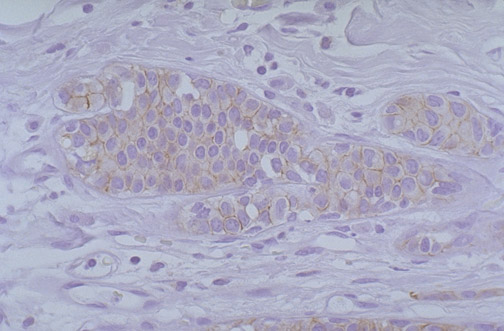

There is minimal perimembranous staining for HER2-neu (C-erb B2), with a score of 1+, classified as negative, for this breast carcinoma.